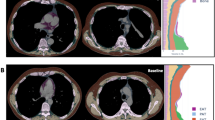

Exemplary in- and output of fully automated CT-based body composition analysis (BCA). (A) Visualization of feature extraction for BCA and marker aggregation. BCA network detects the different BCA features within the chest CT scan. Those raw features are combined with bone to calculate body size-adjusted biomarkers. The tissues are encoded in colors as follows: pink: bone, yellow: muscle, orange-brown: subcutaneous adipose tissue (SAT), purple: epicardial adipose tissue (EAT), light blue: paracardial adipose tissue (PAT) and turquoise: inter- and intramuscular adipose tissue (IMAT). (B) Exemplary chest CT in axial view before (left) and after (right) elexacaftor/tezacaftor/ivacaftor therapy showing decreasing bronchiectasis wall thickening and regredient mucus impaction. (C) Exemplary chest CT in axial view showing increased proportion of subcutaneous adipose tissue (SAT, orange-brown) and increased inter- and intramuscular adipose tissue (IMAT, turquoise) after elexacaftor/tezacaftor/ivacaftor therapy.